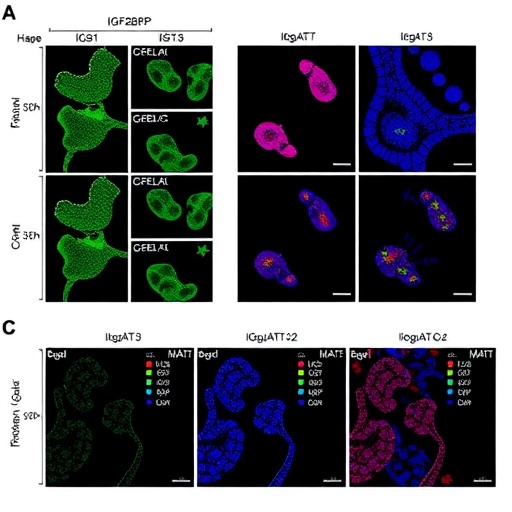

The insulin-like growth factor 2 mRNA-binding protein 3 (IGF2BP3) emerges as a pivotal player in colorectal cancer progression. It has been associated with tumor growth and metastasis, functioning as an oncofetal protein that influences various cellular processes. Through its binding to target mRNAs, it regulates their stability and translation, ultimately promoting cancer cell proliferation and survival. The research expands on existing knowledge by demonstrating that IGF2BP3 acts in concert with IL6ST and STAT3 to create a self-amplifying loop that enhances tumor aggressiveness.

IL6ST, or the interleukin 6 signal transducer, is a critical component of the inflammatory response. Recent findings illustrate its role not just in normal tissue repair and healing, but also in tumor biology. The connection between IL6ST and colorectal cancer progression is underscored by the cytokine milieu within the tumor microenvironment, effectively facilitating a pro-tumorigenic state. The study posits that high levels of IL6ST can lead to increased activation of the STAT3 pathway, further driving the malignant behavior of colorectal cancer cells.

The activation of the STAT3 transcription factor is at the heart of numerous oncogenic processes. When IL6ST binds its ligands, it activates the JAK-STAT signaling cascade, culminating in the phosphorylation of STAT3. This activation allows STAT3 to translocate to the nucleus, driving the expression of genes critical for cell proliferation, survival, and invasion. The elucidation of this pathway by Liu and Zhou positions STAT3 as not only a biomarker of disease progression but a potential therapeutic target that could interrupt the feedback loop fueling cancer advancement.

The study’s findings hold substantial implications for future research and clinical practice. By characterizing the molecular events within this feedback loop, the research delineates a potential roadmap for novel therapeutic strategies aimed at disrupting IGF2BP3, IL6ST, and STAT3 interactions. Targeted therapies that could downregulate or inhibit these molecules may render cancer cells more susceptible to conventional treatments, potentially improving patient outcomes.